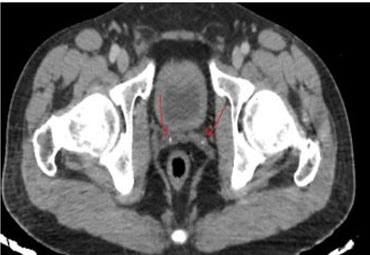

Otherwise, the patient claims primary infertility of 20 years since marriage, he underwent a spermiogram that revealed oligoasthenospermia. Pelvic computed tomography (CT) scans showed calcifications in the prostate (Figure 3) and seminal vesicles (Figure 4), pelvis magnetic resonance imaging (MRI) scan confirmed the CT scan findings.

Figure 3: Pelvic HRCT: microliths in the prostate.